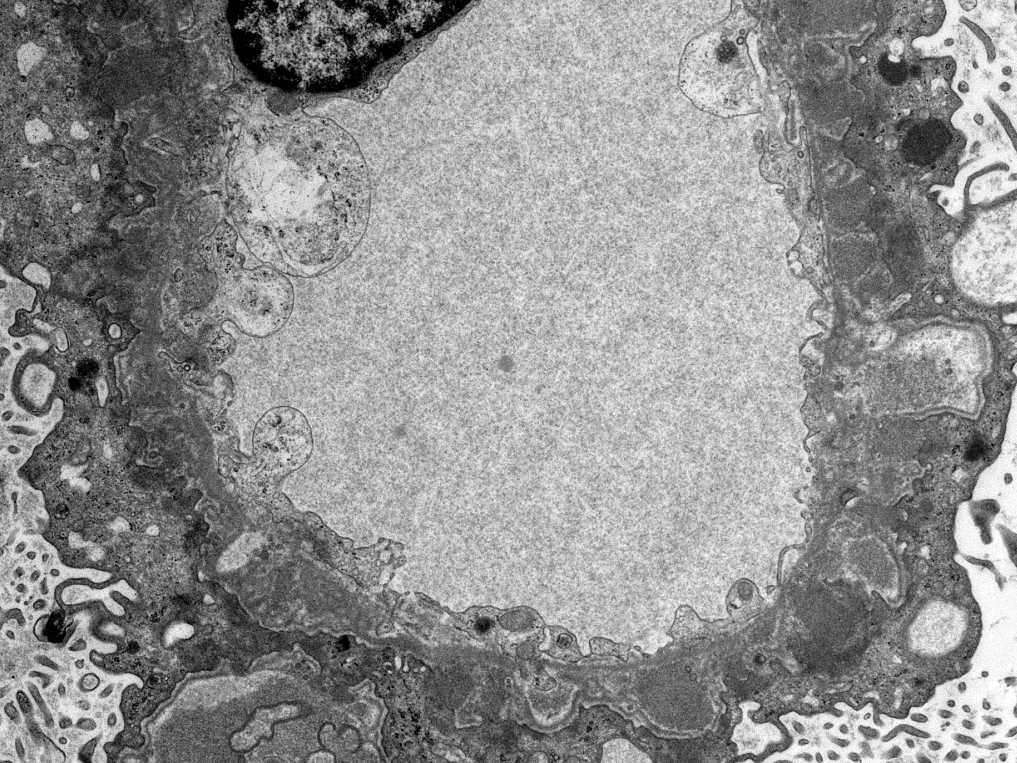

Teenager with nephrotic syndrome. Biopsy revealed unusual case of membranous nephropathy in a peds patient. PLA2R positive (IHC). PLA2R most common antigen in peds MN. EXT2 also common, SEMA3B less common. ( https://t.co/zEASwdQXIe)

#renalpath #pathsky #nephsky